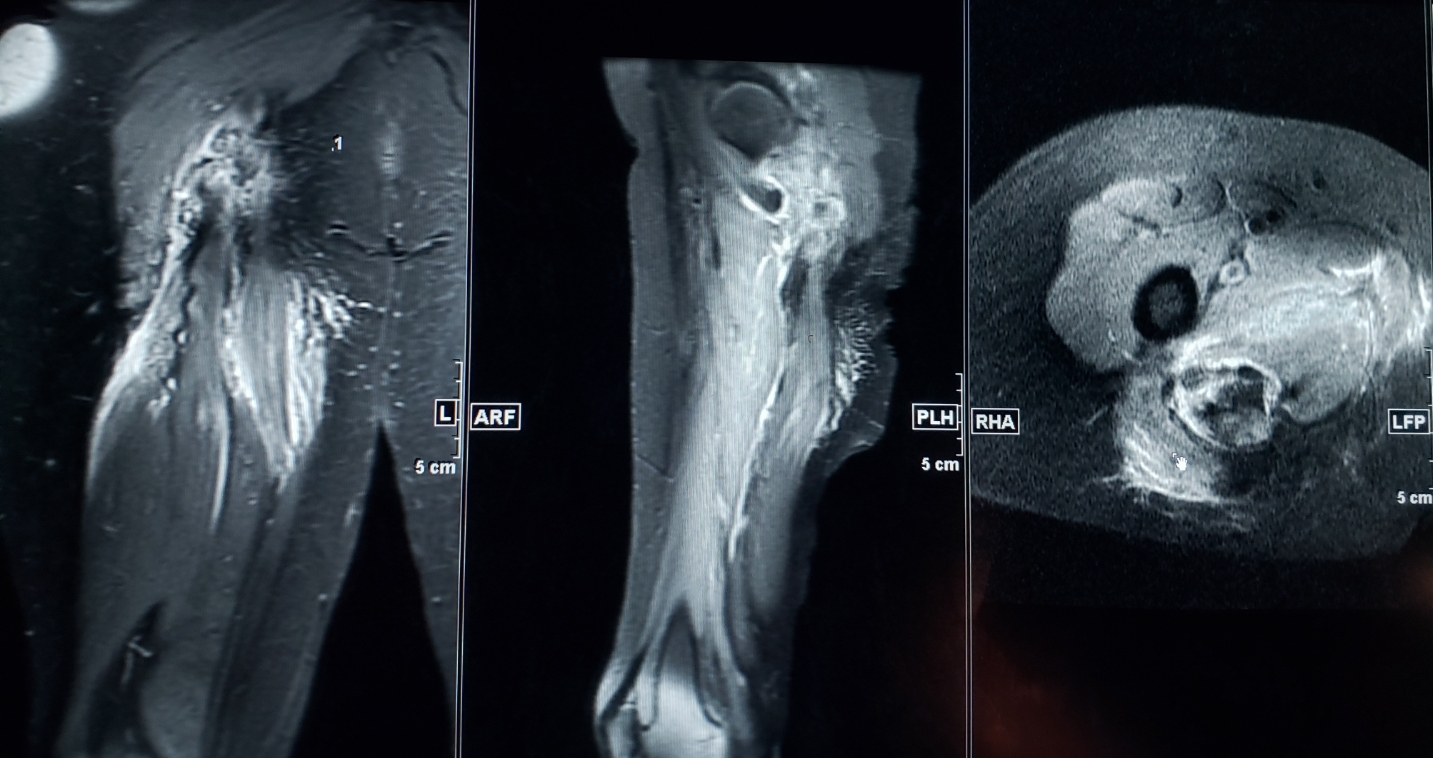

University of Toledo Radiology Common Hamstring Tendon Rupture Hamstring Pull Vs Tear Learn how to prevent, diagnose and treat it, and when to see a healthcare. a hamstring injury is a tear or strain in the back of your thigh. learn the difference between a hamstring pull and a hamstring tear, and why it matters for your treatment. a hamstring injury is a strain or pull of one of. Hamstring Pull Vs Tear.